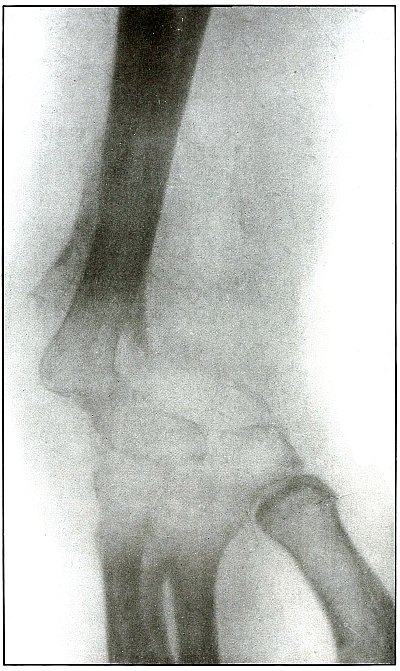

Plate 60.

_

[Pg 131]

Rifle—Plate 60.

LOWER EXTREMITY.

Gunshot Fracture of the Tibia and Fibula,

with Lodgment of the Missile.

The course of the bullet was diagonal from within outward and backward about the middle of the leg, with the impact tangential on the tibia and direct on the fibula. The bullet lies just behind the tibia.

It is apparent that the bullet has been greatly deformed and that its jacket has been badly torn from the core. The force of impact on the object from which it ricocheted must have been contributed by the velocity of short range, which reduced the striking energy so greatly that the bullet was lodged by the resistance of the tibia and fibula.

The wound was not infected, and callus formation shows that repair has begun.

The treatment in such cases, without infection, is noninterference. The lodgment of the missile need not prejudicate the prognosis, and certainly the additional damage in the search for the bullet is not warranted, except under special indications. [Pg 132]